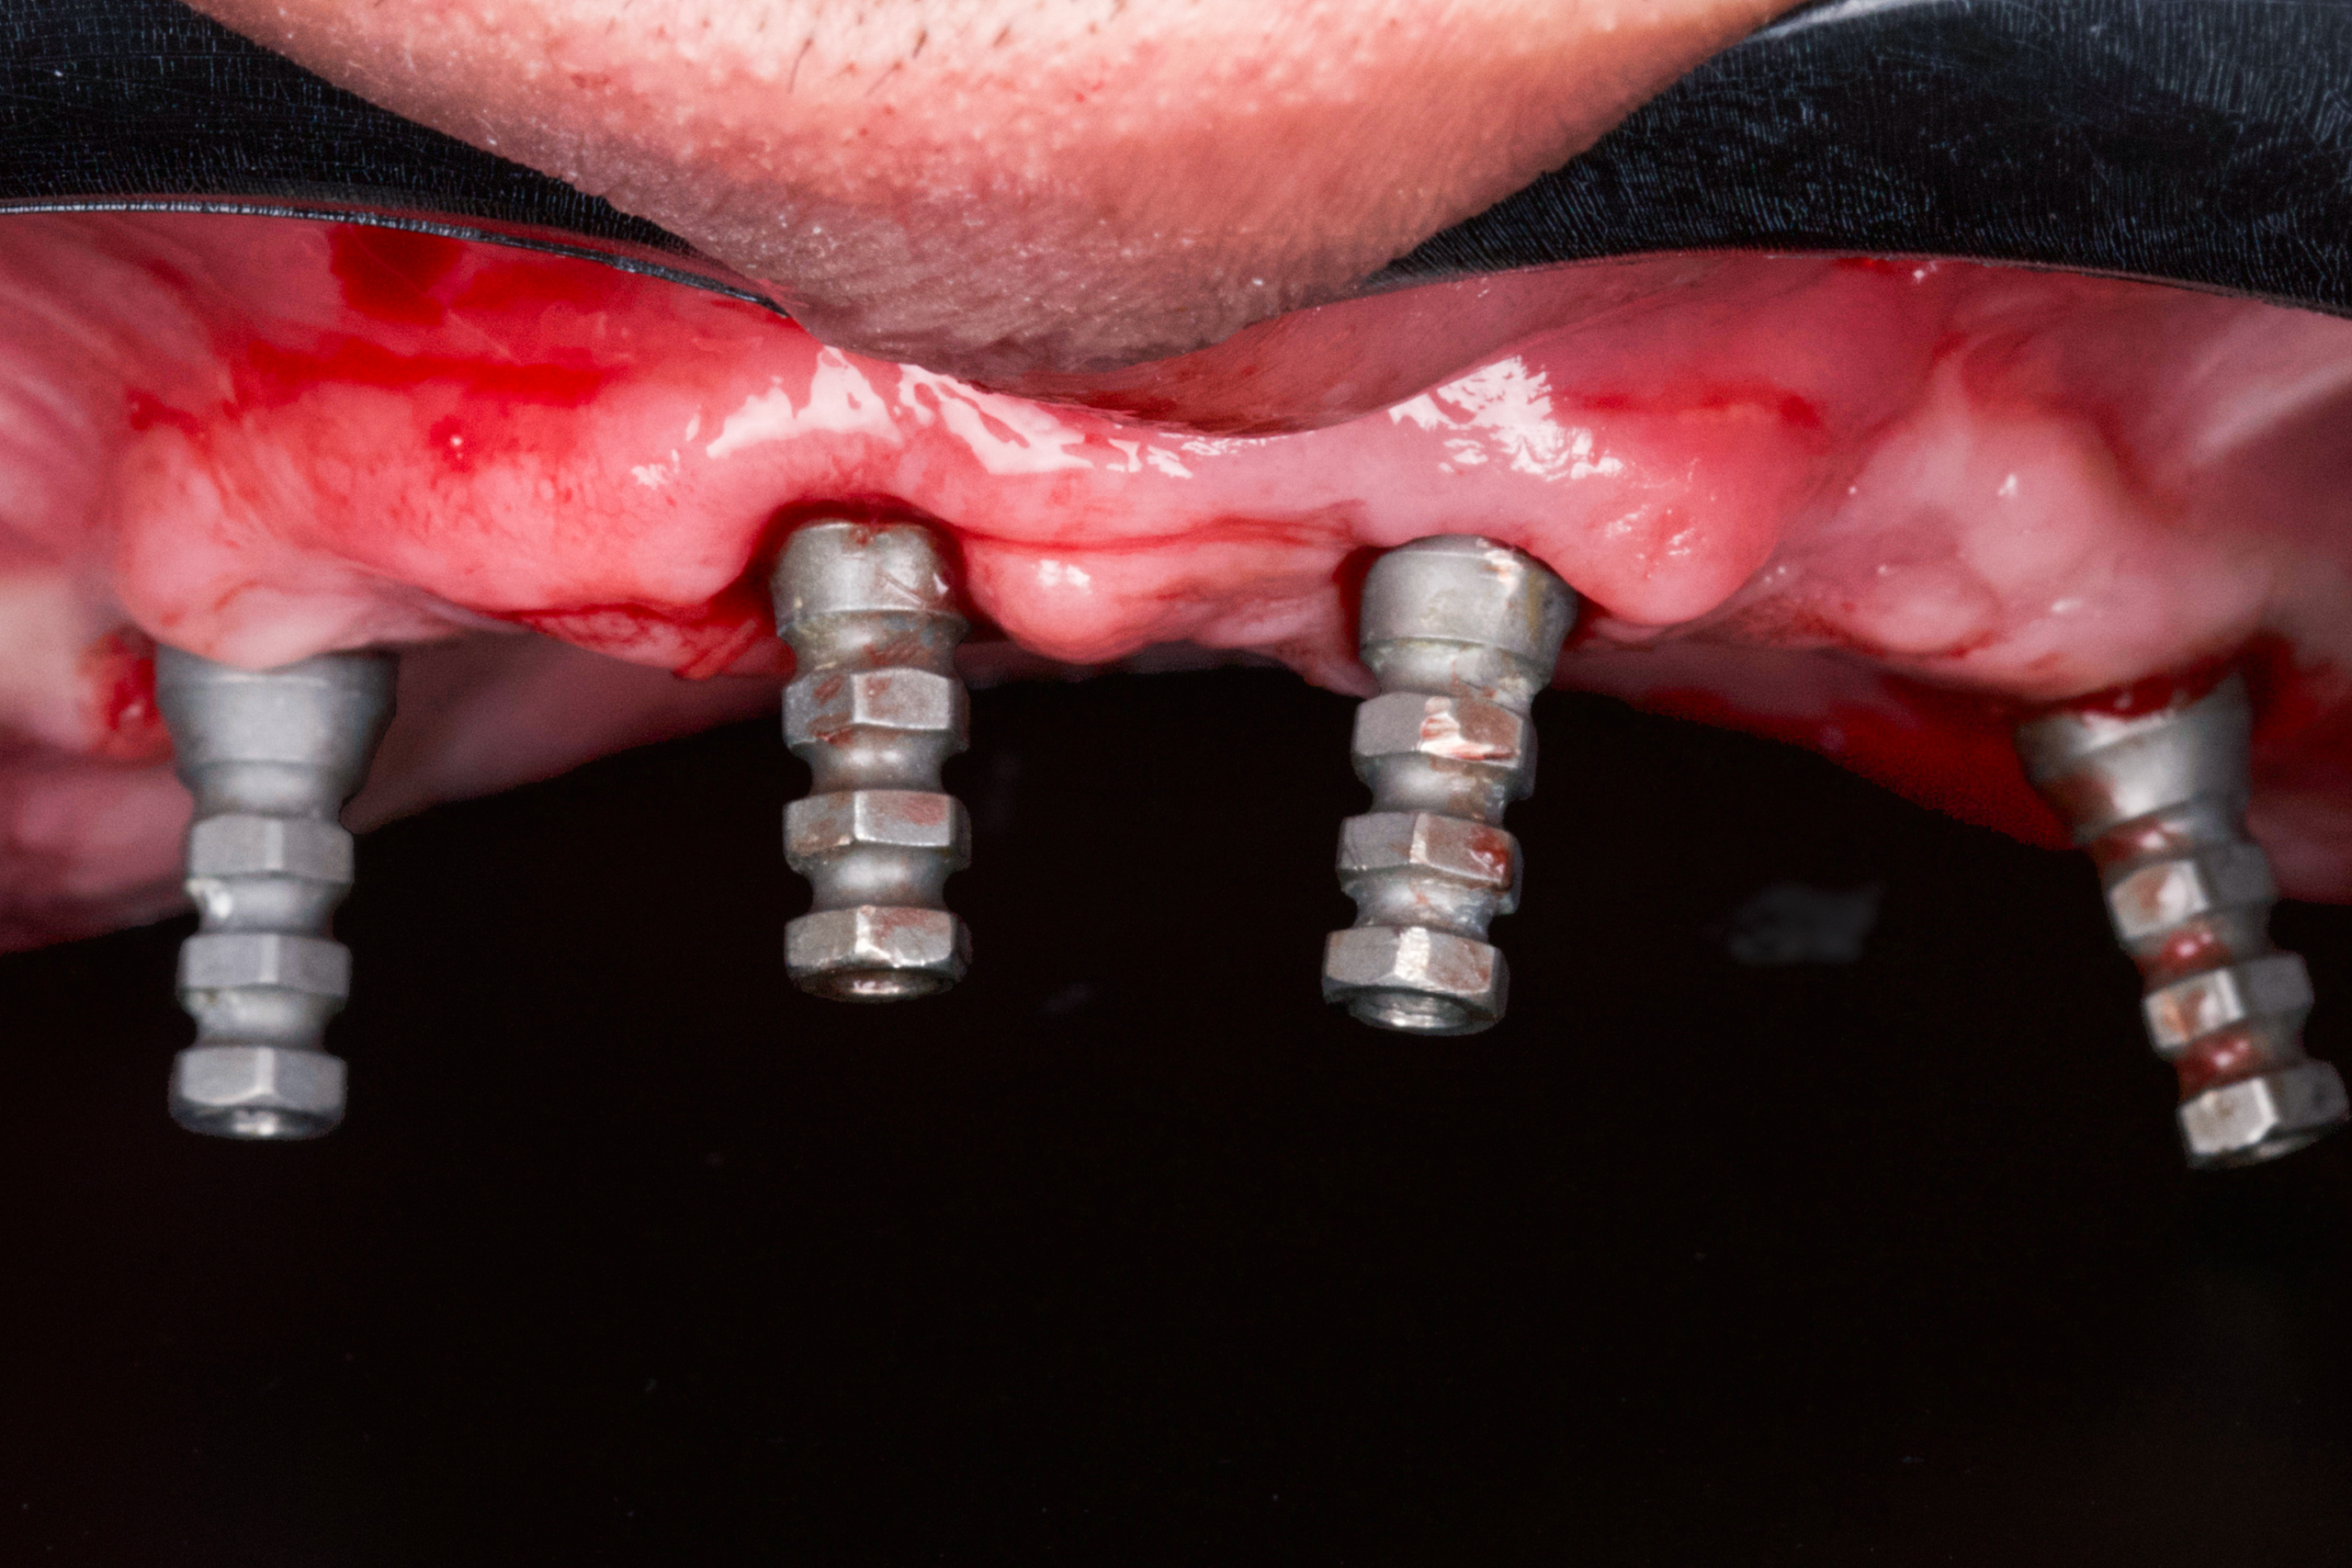

- Removal and correction of the failed lower-jaw restoration

- Seamless implant placement using digital guides

- No incisions, no sutures, minimal bleeding

In only 3 hours, James received a complete upper-jaw reconstruction and a corrected lower-arch restoration using a fully flapless implant technique.